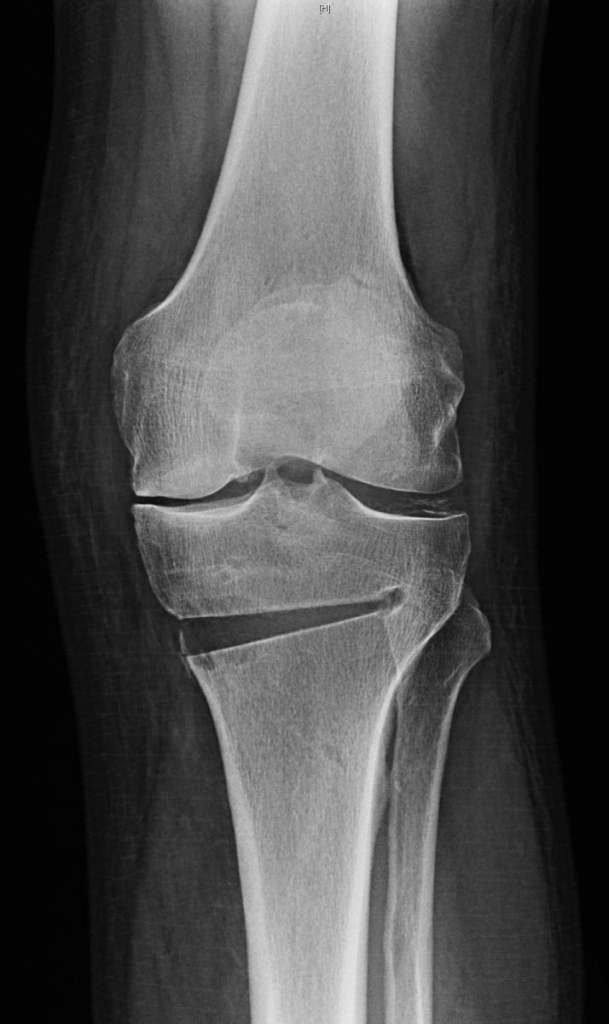

Ko tieši dara, veicot apakšstilba osteotomiju? Šāda operācija parasti norit 40 līdz 60 minūtes, pacientam atrodoties spinālajā narkozē. Veicamā operācija ir iepriekš rūpīgi plānota, nosakot korekcijas leņķi. Osteotomijas operācijā tiek veikta daļēja apakšstilba kaula iezāģēšana. Atverot osteotomijas vietu tiek pacelta ceļa locītavas virsma, un līdz ar to mainās kājas ass, un locītavas slodze ir izbalansēta.

Atvērtajā kaula daļā tiek likts kaula autotransplantāts, kas ņemts no paša pacienta kaula, vai arī sintētisks materiāls, kas veicina jaunu kaulaudu veidošanos. Ar laiku – vidēji divi līdz četri mēneši – kaula atvērums dabiski aizpildās ar jauniem kaulaudiem. Lai paātrinātu šos šūnu atjaunojošos procesus, iespējams izmantot PRP (plazma) jeb trombocītiem un augšanas faktoriem piesātinātu materiālu, kas tiek iegūts no paša pacienta asins parauga.

Savukārt, lai šajā dzīšanas procesā kaula atvērums būtu stabils, tiek izmantoti stabilizējoši implanti. “Es esmu izvēlējies implantu sistēmu, kas ir no droša, biosaderīga poliēterēterketona materiāla un nodrošina papildus operētās vietas stabilitāti sadzīšanas laikā. Tas kalpo kā ķīlis, ko ievieto atvērumā, stabilizējot koriģēto leņķi,” skaidro Dr K.Ūdris.